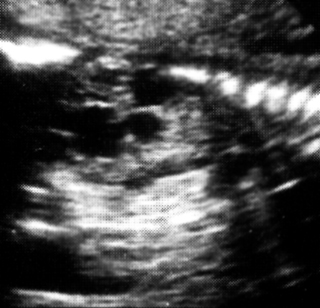

Υπερηχογραφικά, παρατηρείται χαρακτηριστικά το σημείο της διπλής φυσαλίδας,

που οφείλεται στο διατεταμένο στόμαχο και το εγγύς τμήμα του δωδεκαδακτύλου,

σε συνδυασμό με υδράμνιο (στο 17-53% των περιπτώσεων) (εικόνα 20). Παρόλο που

η χαρακτηριστική διπλή φυσαλίδα μπορεί να παρατηρηθεί από τις 20 εβδομάδες,

συνήθως δεν γίνεται εμφανής πριν τις 25 εβδομάδες της κύησης. Η επιβίωση μετά

| Εικόνα 20. Ατρησία 12δακτύλου. | Εικόνα 21. Ατρησία ειλεού. |